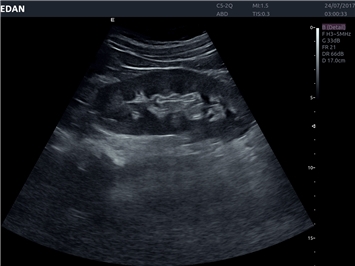

• Общей визуализации

Общая визуализация:

Да